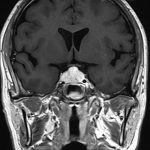

711

'25年12月

60代

良性頭蓋咽頭腫

頭蓋内腫瘍摘出術

No.’25_113 手術前1

No.’25_113 手術前2

No.’25_113 摘出 前

No.’25_113  摘出 中

No.’25_113 摘出 後